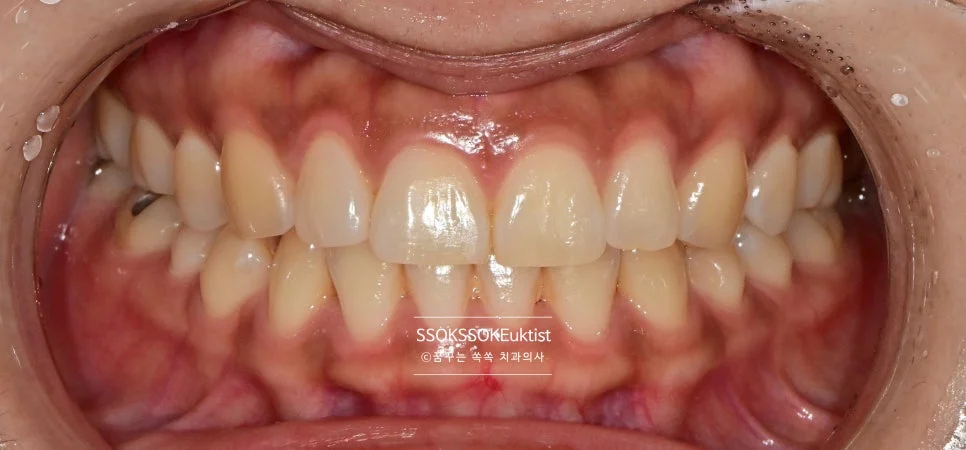

그리고 안쪽에 닿는 점을 조정하여 치아가 벌어지는 경향을 최소화해주면 치료는 종결됩니다.

한 달 정도 후의 모습으로, 비교적 잘 유지되고 있는 것을 확인할 수 있습니다!